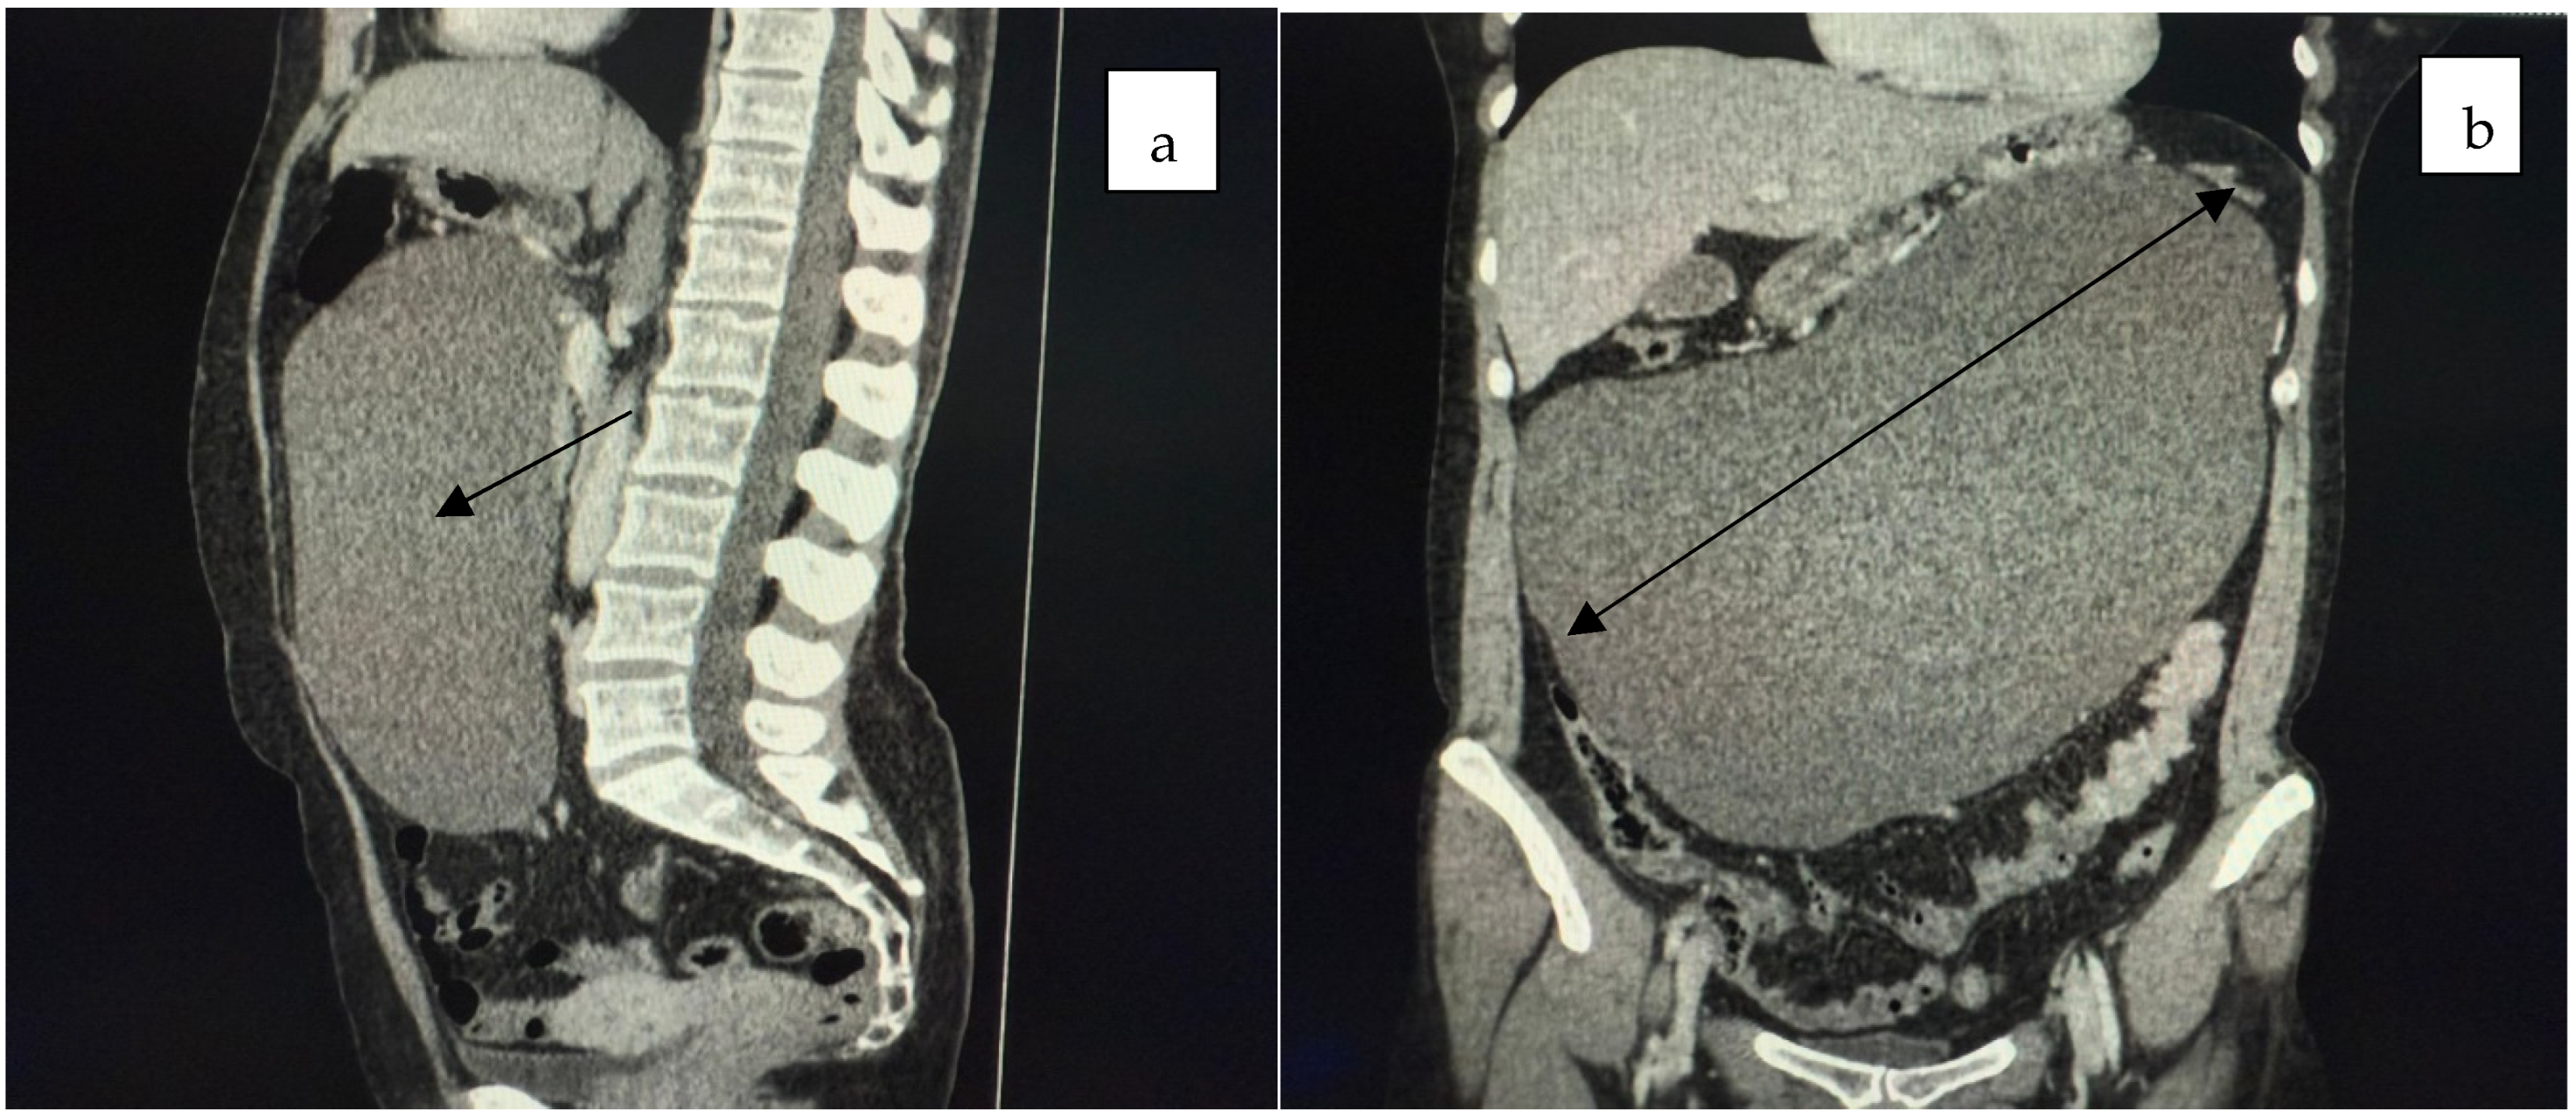

2. Case Presentation